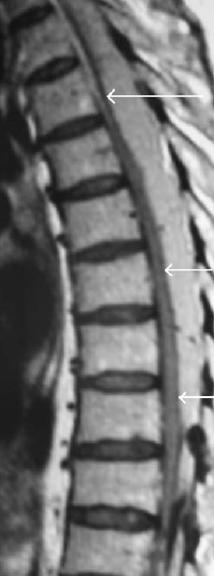

- epidural haematoma after SCS implant

epidural haematoma   click the image to see the case history and references